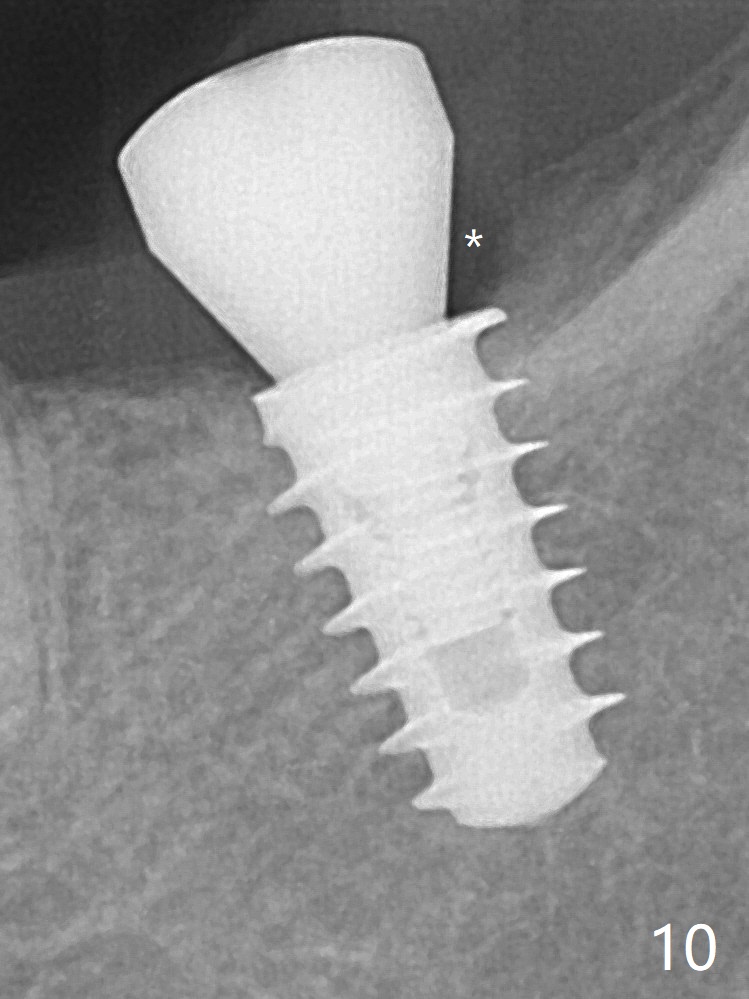

In fact, the mesial crest of the socket could be used as a more secure landmark (bony vs. soft tissue) for osteotomy depth (Fig.4 arrowhead) with drill stopper. To place the implant subcrestal, the initial osteotomy should be 1-2 mm deeper. When she returns 2 years 9 months postop, the wound has healed. The implant needs to be uncovered. Make sure to have clearance for a healing abutment. Use sensor 1 for PAs before and after uncover. The implant appears to be tilted distal. An angled abutment may be required. Take PA for seating confirmation. Guided surgery is preferable. The implant plateau is covered by the bone 2 years 9 months postop (Fig.8 *). The healing screw is removed with difficulty, while a 6x3 mm healing abutment is placed with resistance, probably related to interference from the distal crest (Fig.9 *). It is much easier with removal of the crest bone using surgical bur, because of clearance (Fig.10 *). It is the best to have a particular drill to remove the excess bone. There is no interference to insert and torque a 5x4(2) mm pair abutment 2 weeks post uncover (Fig.11). Due to poor trajectory (guide necessity) and tight proximal contact, the crown is not completely seated (Fig.12). However, the abutment screw is unlikely to get loose in the future.